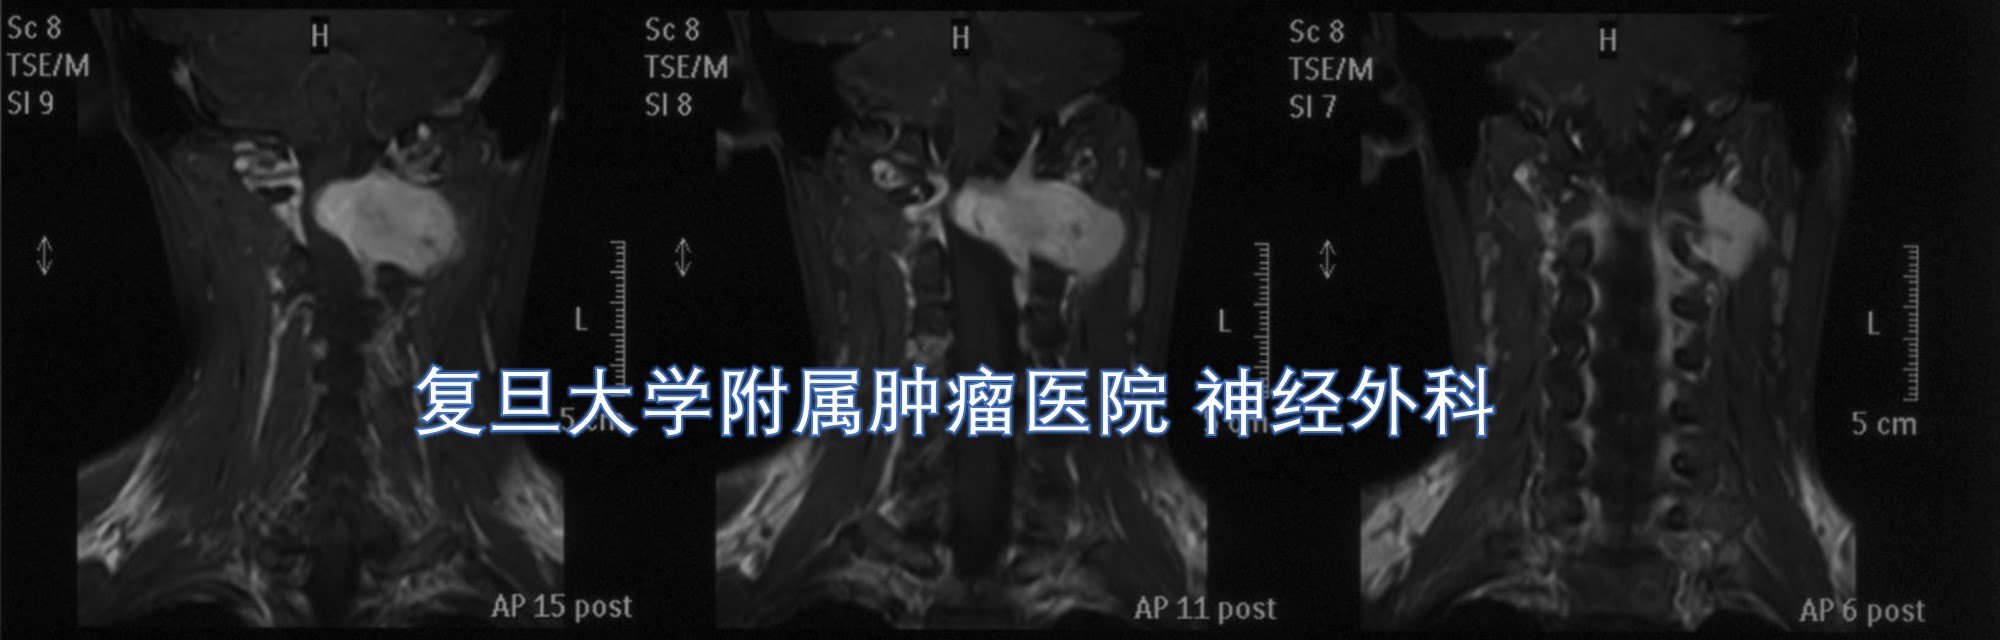

颈椎磁共振提示:颈1水平椎管内外沟通性肿瘤,伴有左侧椎间孔扩大,颈髓受压明显,肿瘤均匀强化,与周围血管神经管系密切。

结合患者病史及影像学表现,术前首先考虑为神经鞘瘤可能。